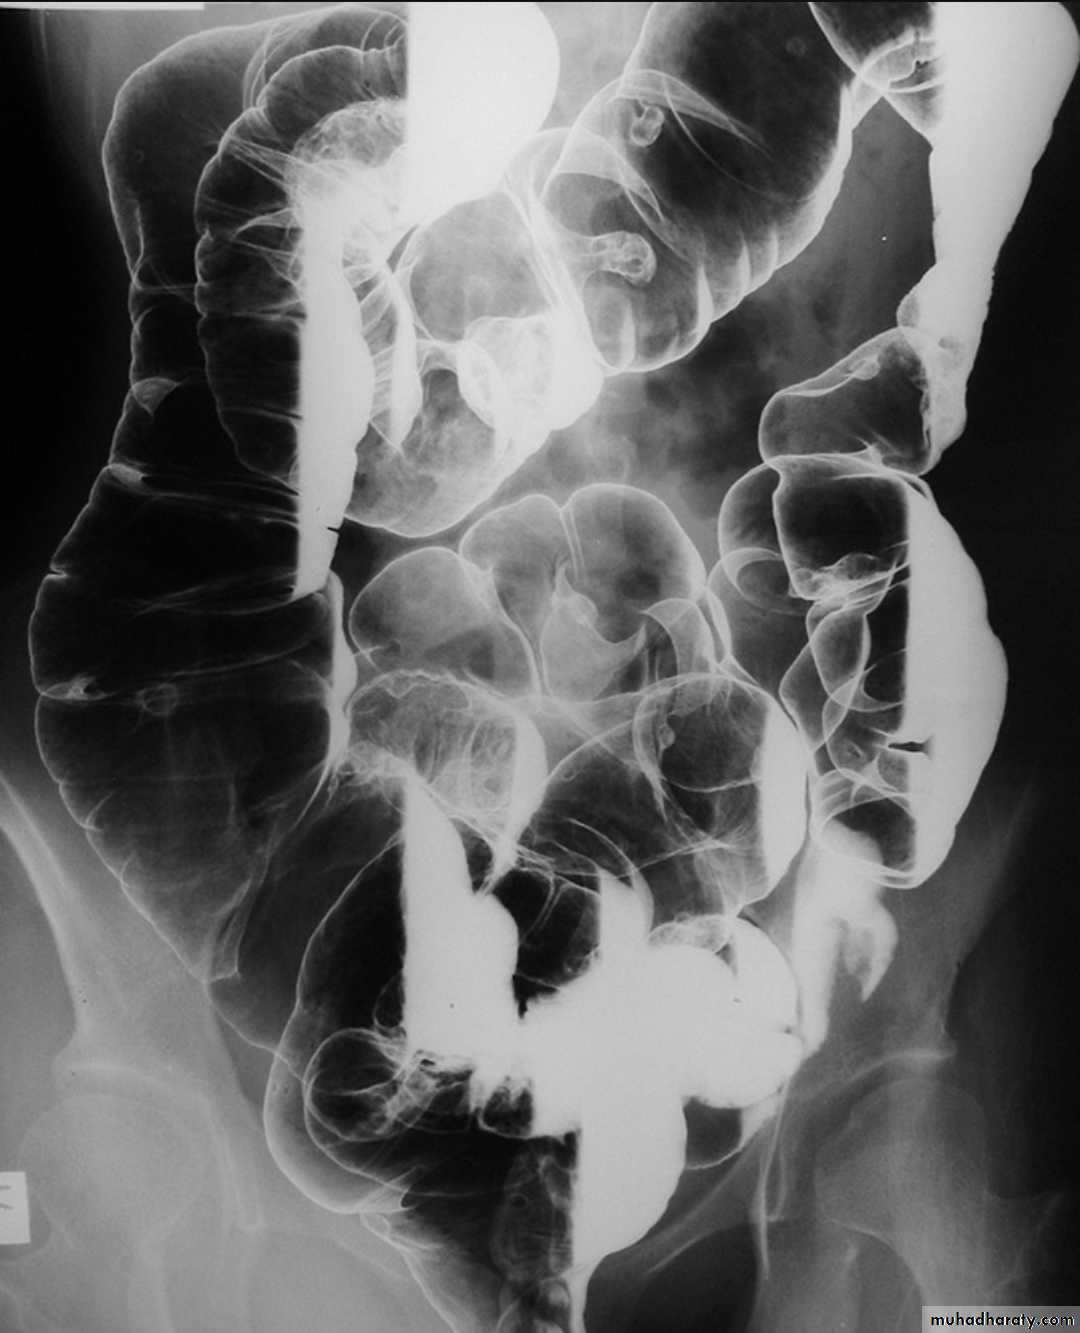

Familial adenomatous polyposis syndrome

(FAPS) is characterized by the presence of hundreds of adenomatous polyps in the colon. It is the most common of the polyposis syndromes.Radiographic features

FAPS has a varied imaging appearance and demonstrate innumerable polyps. Imaging usually underestimates the number of polyps because most are <5mm in size.

It is a predisposition to colorectal carcinoma (CRC)